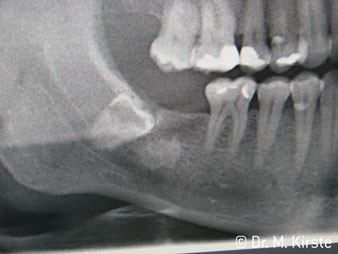

The 45° angle of the handpiece has been specially selected for its wide range of advantages. Colleagues who work in surgery, and for whom this handpiece was primarily developed, will soon appreciate the ability to work efficiently in very restricted spaces. In wisdom tooth extractions in particular (fig. 2) there is no need for large-scale spreading of the soft tissues in the cheek region (fig. 3). The design of the handpiece head combined with turning the head slightly during preparation allows work to be carried out quickly and safely in the retromolar region.

The professional design of the bearings inside the handpiece head guarantees quiet running of the bur; this makes for an impressively atraumatic cut in the separation of tooth and root (fig. 4-9).

Fig. 4